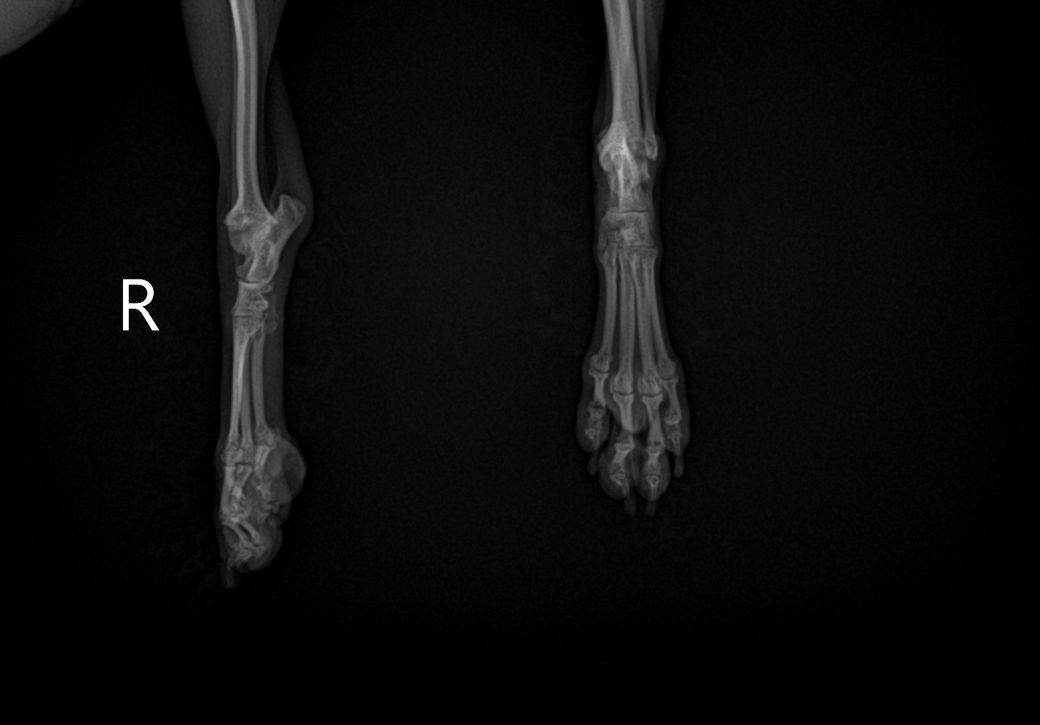

담당 의사선생님께서 십자인대의 문제는 확인이 어렵다고 하셨는데, 보통 X-ray로 확인하지 않나요..?ㅠㅠ 그래서 아하에 계시는 수의사 분들께 병원에서 받아온 X-ray 사진과 병원에 진료 후 내려놨을 때 걷는 영상을 첨부하오니, 100%가아니더라도 십자 인대 수술이 필요해보이는지, 다른 소견은 없는지 등의 진단을 부탁드립니다..!ㅠㅠ

30cm가 이니라 10여도 터질 십자인대는 터집니다. 다만 첨부한 사진에서 양쪽 뒷다리의 측면 사진이 모두 첨부되어야 관절낭을 중심으로 비교 평가할 수 있는데 사진이 누락되어 판단할 수 없습니다. 다만 주관적으로 2번째 첨부 사진에서 아킬레스건의 부종 양상이 관찰되고 슬개골 관절낭의 심한 종창은 보이지 않아 십자인대 단열보다는 아킬레스건 부분단열을 먼저 고려해야 할것으로 보입니다. 주치의의 지시에 따라 평가 진행해도 크게 무방합니다.